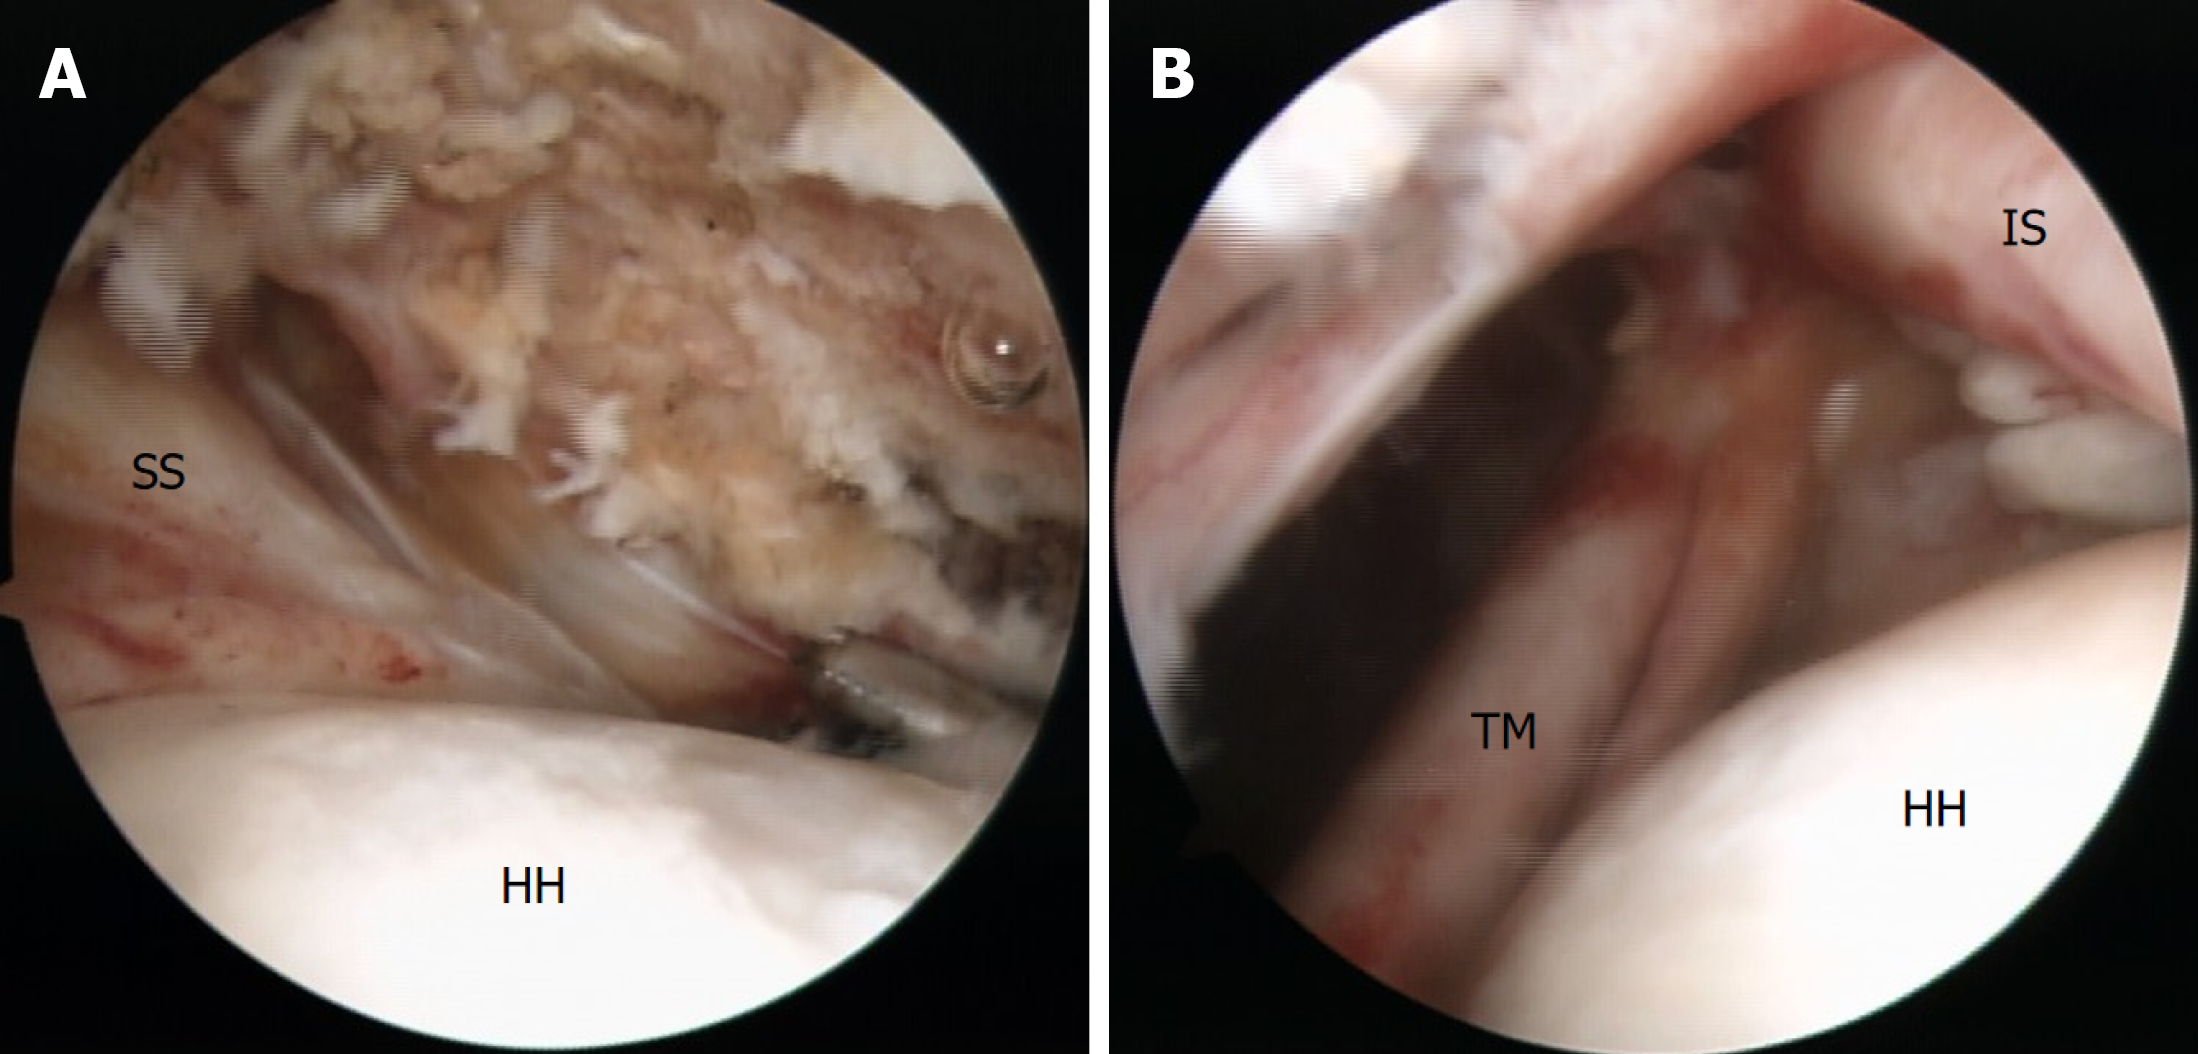

Figure 4 Arthroscopic findings.

A: Near-complete intra-articular tear and complete medial dislocation of the long head of the biceps tendon from the bicipital groove; B: Restoration of the anatomical continuity of the subscapularis tendon after single-row repair. 1: Long head of the biceps tendon. G: Glenoid; HH: Humeral head; SSc: Subscapularis.